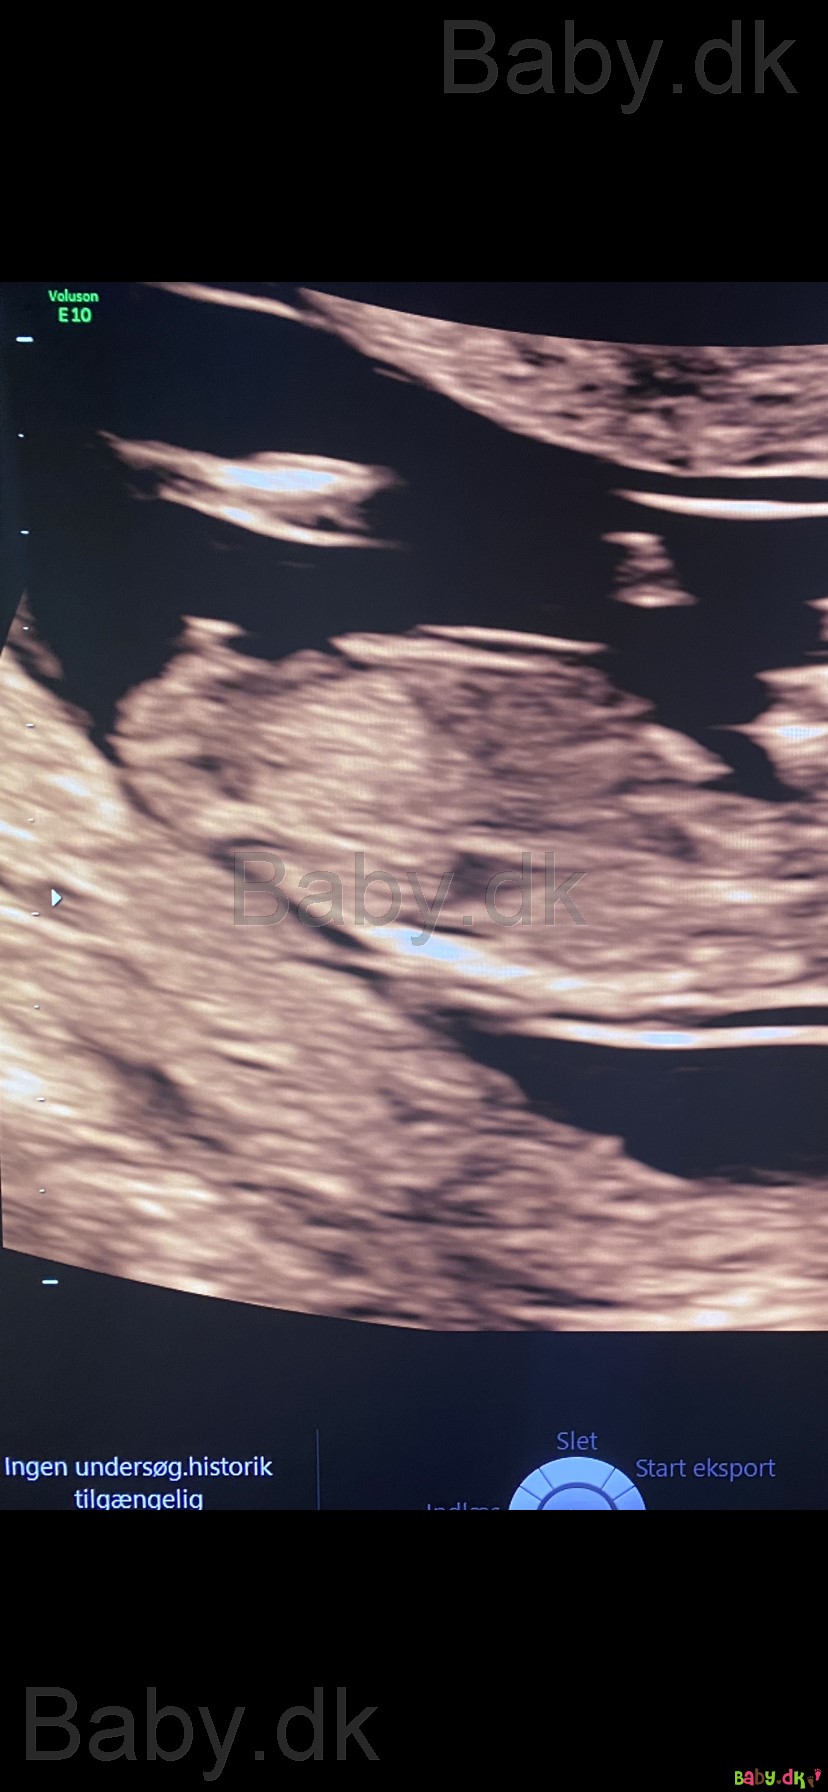

Kan I hjælpe mig med at gætte kønnet? Er 12+4 da jeg var til scanning

Meget flot drenge-nub :-)

Helt klart en dreng

Er sikker på en dreng ��